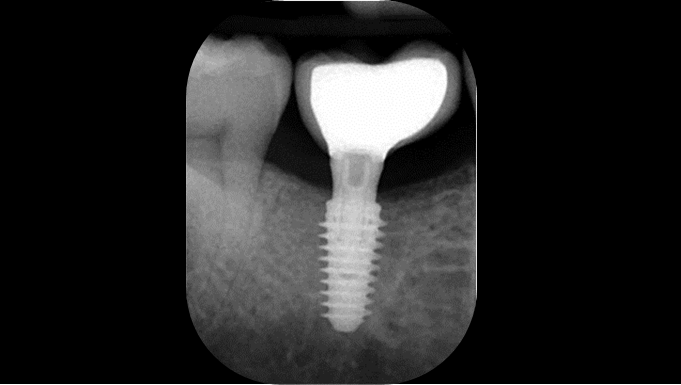

Klinikinis atvejis: Vėlyvoji implantacija: viršutinio žandikaulio ančio dugno elevacija, implanto sriegimas ir kraštinė kaulo regeneracija;

- Dr. Irfan Abas klinikinis atvejis -

Vėlyvoji implantacija, ančio dugno elevacija, ančio dugno elevacija atviru būdu, kraštinė kaulo regeneracija, Dr. Irfan Abas, AnyRidge, MiLA chirurginis rinkinys, kaulo regeneracija;

AnyRidge implantų sistema, MILA chirurginis rinkinys;